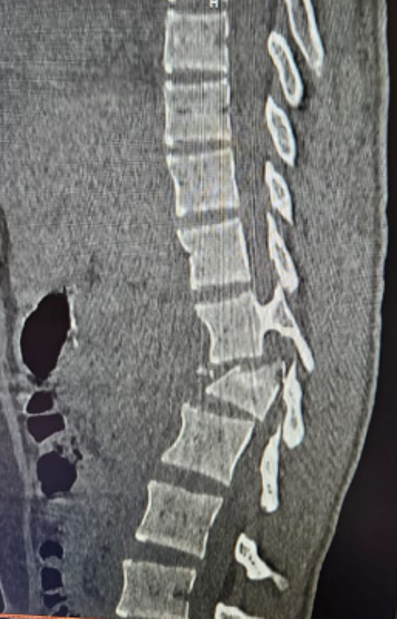

Broken bones are stabilized with screws, rods, or cages to protect the spinal cord and restore alignment.

Stabilization

Rods, screws, or cages are used to restore alignment and protect the spinal cord.